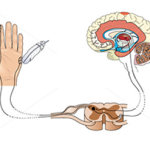

痛みというのは切り傷のように怪我(組織損傷)をするとその場所にある痛みを感じる神経が刺激されて脊髄から脳へ電気信号が流れて痛いと感じます。

しびれは正座をすることでほとんどの方が一度は経験したことがあると思いますが、正座のようにずっと圧迫していると神経に血液が流れなくなって今度はその血流不足の危険を知らせるために神経に過剰な電気が流れます。これがしびれとして感じているものです。